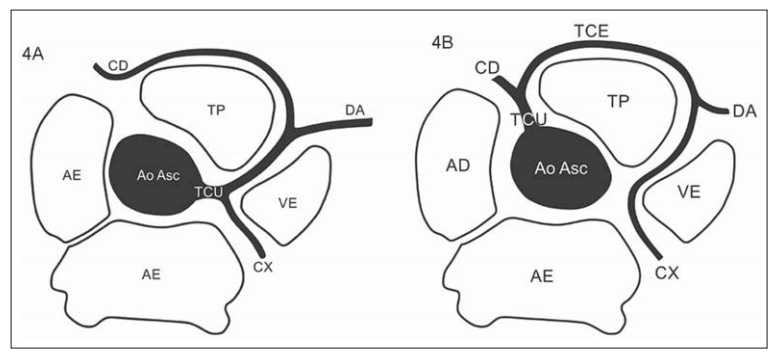

Tronc unique

- Pas de variante Maligne

Tronc coronarien unique à départ de la CD

Depart CD et CG du sinus de valsalva droit, passant devant le tronc pulmonaire

Depart CD et CG du sinus de valsalva droit, passant devant le tronc pulmonaire